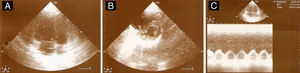

Objetivamente, apresentava-se agitada com hipotensão (73/35mmHg), taquicardia (115 bpm), hipoxémia (saturação de O2 em ar ambiente 80%) e polipneia (50 cpm). Sem sinais de trombose venosa profunda (TVP). Fez análises (hemoglobina 12,3g/dL; plaquetas 170x109/L; d-dímeros 2.962 ng/mL e troponina I 0,43 ng/mL (referência <1,50 ng/mL)) e na gasometria arterial realizada já com O2 suplementar a 5 L/min apresentava alcalose respiratória (pH 7,49; pO2 105mmHg; pCO2 28mmHg, HCO3− 20,9 mmol/L e saturação de O2 98%). Realizou eletrocardiograma (ECG), que mostrou taquicardia sinusal e sinais de sobrecarga no ventrículo direito (VD) (Figura 1) confirmados por ecocardiograma transtorácico (ETT) à cabeceira (Figura 2).

ETT (A) Plano apical de 4 câmaras telediastólico com dilatação do ventrículo direito, movimento paradoxal do septo intraventricular e PSAP estimada em 65mmHg, (B) no plano paraesternal curto-eixo com retificação diastólica do septo intraventricular em relação com hipertensão pulmonar e (C) função sistólica do ventrículo direito preservada (TAPSE 23mm).